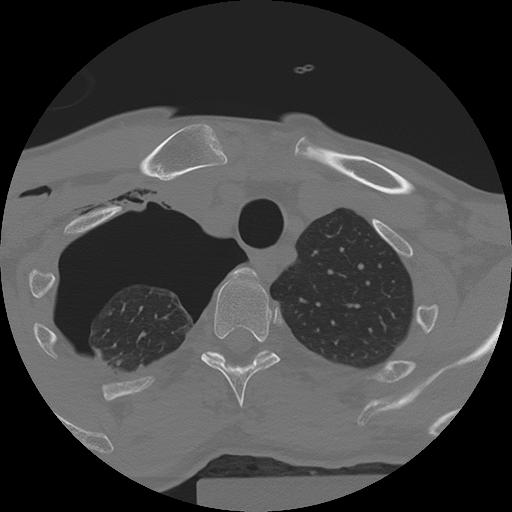

11 HUESO,,Axial,2.0,HUESO,,